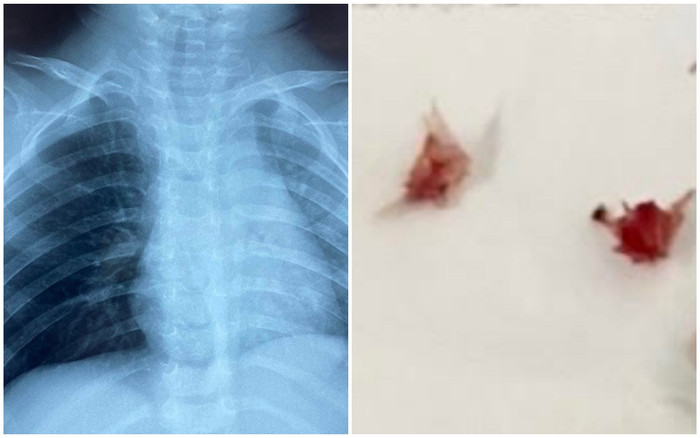

Các bác sĩ đã gắp ra mảnh xương lươn. (Ảnh: BV Nhi Đồng 1).

ThS.BS Phú Quốc Việt (khoa tai mũi họng, BV Nhi Đồng 1) cùng ê kíp bác sĩ đã gắp thành công các mảnh xương lươn sắc nhọn ở phế quản gốc phải và ở phế quản hạ phân thùy trên bên phải.

Các mảnh xương cắm sâu vào niêm mạc chỉ lộ phần đuôi xương khiến việc soi gắp dị vật gặp nhiều khó khăn.